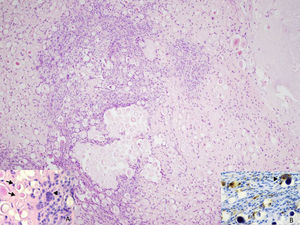

Abundant psammoma bodies and proliferation of fusiform mononuclear cells (H&E 100×). (A) Presence of spherical calcifications (arrows) and multinuclear giant cells (arrowhead) (H&E 200×). (B) CD68 immunostaining reveals the presence of disseminated mononuclear cells surrounding the calcifications and multinuclear giant cells (arrowhead) (CD68 200×).

The diagnosis was tenosynovitis with psammomatous calcification. Although it can be considered part of the spectrum of tumor lesions with calcification, its clinical and histological features indicate that it is a distinct entity. It is very seldom observed, and rarely reported in the medical literature.1–4 It can be described clinically as a single subcutaneous nodule or mass that is most frequently located in the acral regions of the extremities, predominantly in adult women. The patients mentioned a history of repeated injuries associated with their occupation or related to sports.2 The lesions were situated in tendon or in peritendinous soft tissue. From the histological point of view, they were found to be a proliferation composed of histiocytes and (myo) fibroblasts, and the presence of numerous psammoma bodies.